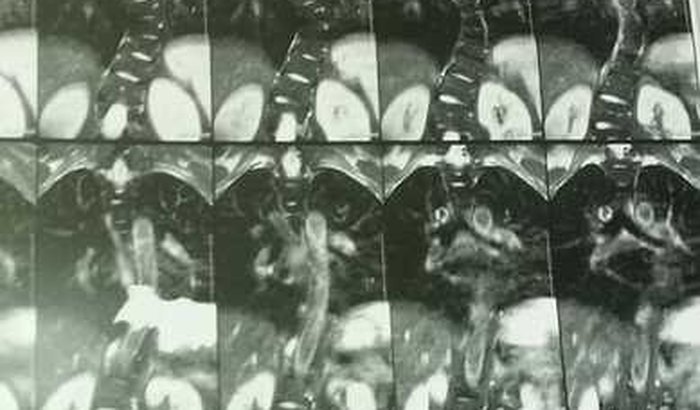

eu sou Leonardo e preciso arrecadar R$ 100.000 para realizar cirurgia de correção de escoliose acompanhada de hipertrofia degenerativa. já estou há mais de dois anos aguardando na fila de espera do sus, para realizar a cirurgia para correção da escoliose. na época em que iniciamos a consulta, a curvatura estava em 39,5 graus, hoje está com 54 graus, duas hernias na cervical, e sinais de hipertrofia degenerativa na coluna vertebral. o que causa dores insuportáveis. estou tomando morfina para poder realizar tarefas simples, porém sem esse e outros medicamentos como gabapentina, pregabalina e amplictil, é difícil viver. diante de toda essa situação resolvi criar essa vaquinha para realizar na rede particular, essa cirurgia. pois no sus o tempo medio, segundo fui informado em minha cidade, de espera é de 5 anos. não dá para esperar. diante de toda essa situação, conto com a ajuda, daqueles que puderem me ajudar. desde já, agradeço de coração.